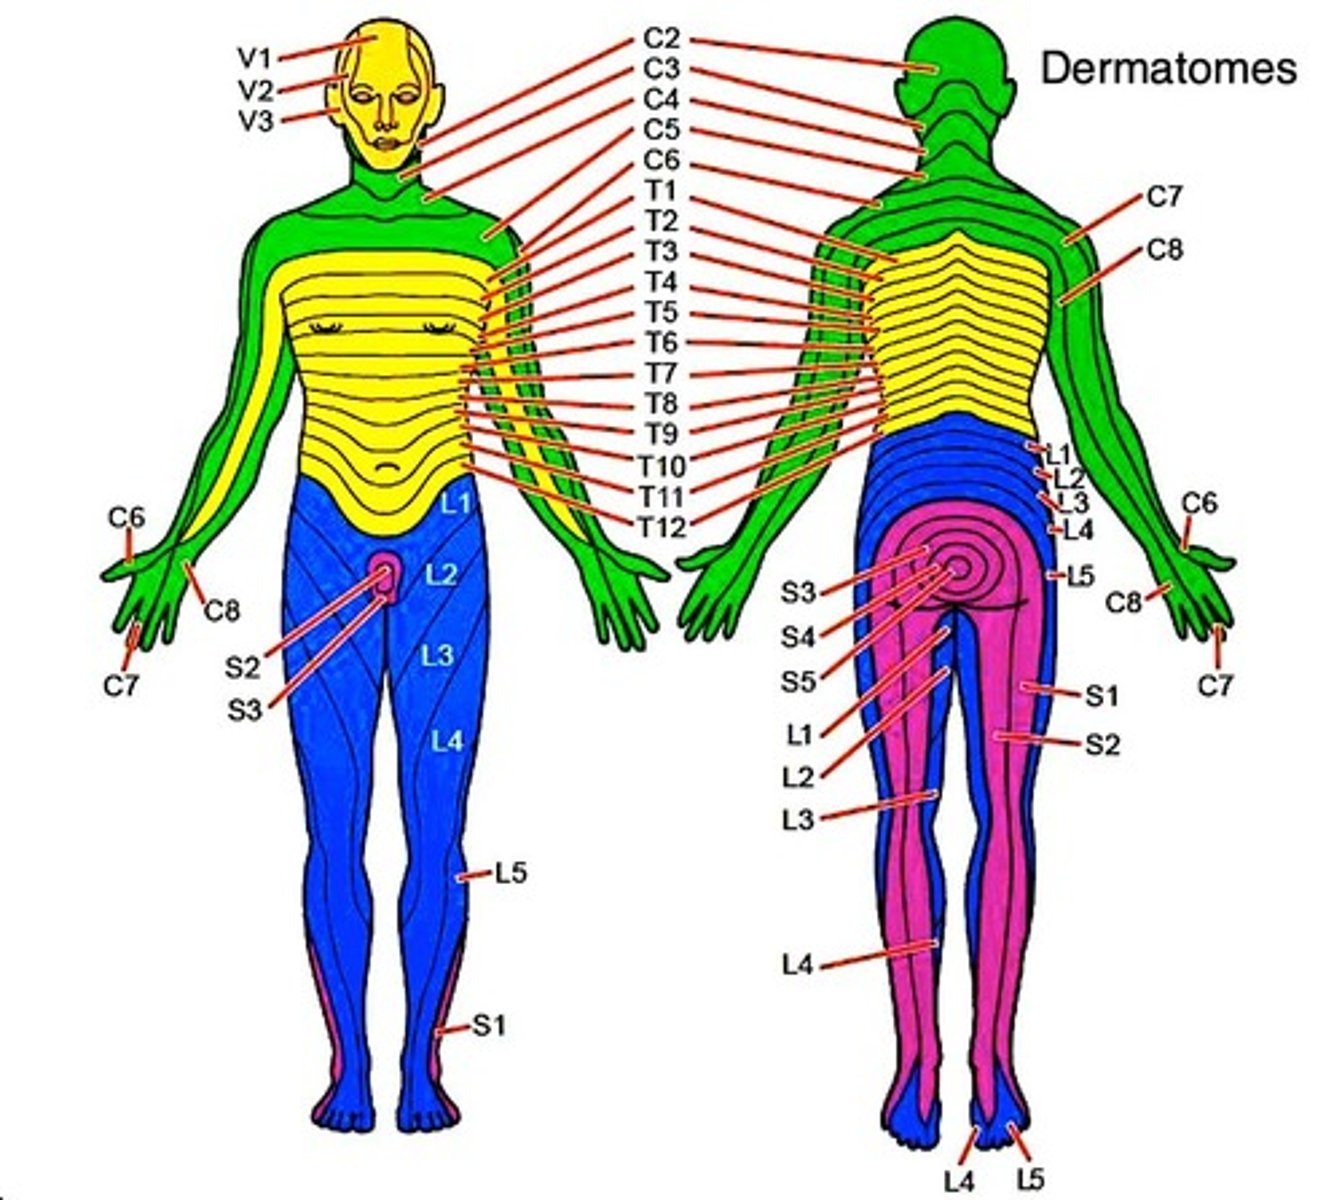

Anterior cerebral artery stroke leads to motor/sensory abnormalities of contralateral leg.

MCA stroke

Middle cerebral artery stroke leads to motor/sensory abnormalities of contralateral arm + face.

Dominant MCA stroke

Usually left MCA stroke can lead to Wernicke or Broca aphasia.

Non-dominant MCA stroke

Usually right MCA stroke can cause hemispatial neglect (inability to draw clockface).

PCA stroke

Posterior cerebral artery stroke leads to contralateral homonymous hemianopsia with macular sparing.

Pain and temperature sensation from contralateral body.

Decussation point

Cross-over (decussation) point is in spinal cord, meaning if, e.g., the left spinothalamic tract is damaged, we lose pain and temperature on the right side of the body below the lesion.

Dorsal columns

Carry vibration + proprioception from ipsilateral body.

9/10 Qs will give bilateral loss of pain and temperature due to lesion of anterior white commissure (decussation point for spinothalamic tract).